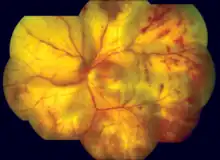

| The typical “cracked mud" appearance of the fundus in progressive outer retinal necrosis[2][3] | |

The diagnosis of Progressive outer retinal necrosis (PORN) syndrome is made primarily through history and physical exam. A patient's medical history of AIDS increases the likelihood of PORN as the diagnosis. An eye exam will show specific hallmark features, including opacified lesions in the peripheral retina without inflammation.